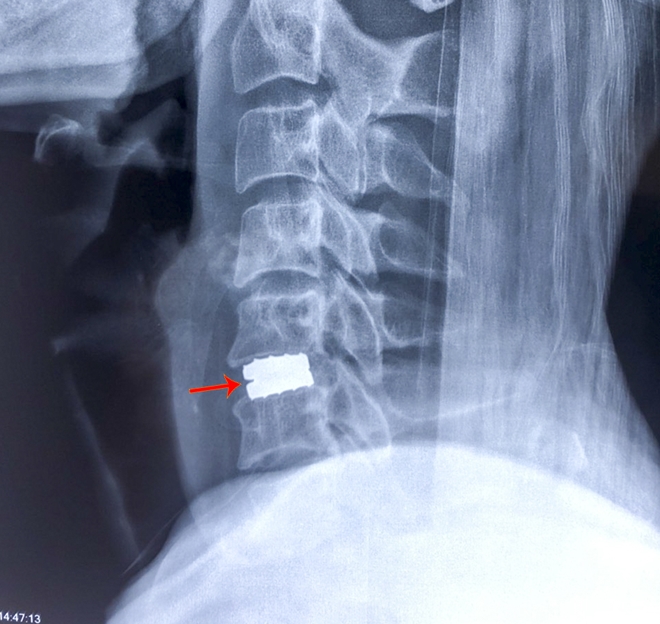

Theo đó, bệnh nhân Bùi Văn Sang (SN 1975, ngụ TP Cần Thơ) có triệu chứng đau cột sống cổ, tê và yếu tay chân đã nhiều tháng, không đi lại được nên đến BVĐKTƯCT thăm khám. Tại đây, qua hình ảnh X-quang; cắt lớp điện toán và cộng hưởng từ cột sống cổ, bệnh nhân được chẩn đoán mắc bệnh lý tuỷ cổ do thoát vị đĩa đệm tầng C5-6 chèn ép tuỷ sống cạnh trung tâm lệch phải. Bệnh nhân được chỉ định thay đĩa đệm nhân tạo đốt sống cổ ở tầng C5-6.

| Hình ảnh chụp cộng hưởng từ trước phẫu thuật. |

| Và sau khi phẫu thuật thành công. |